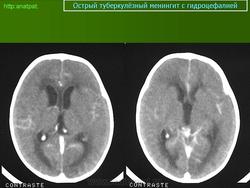

Менингеальный больной туберкулёзом на фоне ВИЧ.

anatpat.unicamp